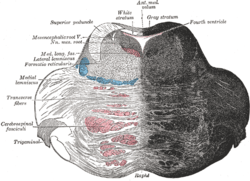

Location and topography of Pons (animation) Axial section of the pons, at its upper part

Axial section of the pons, at its upper part Hind- and mid-brains; posterolateral view

Median sagittal section of brain Nuclei of the pons and brainstem